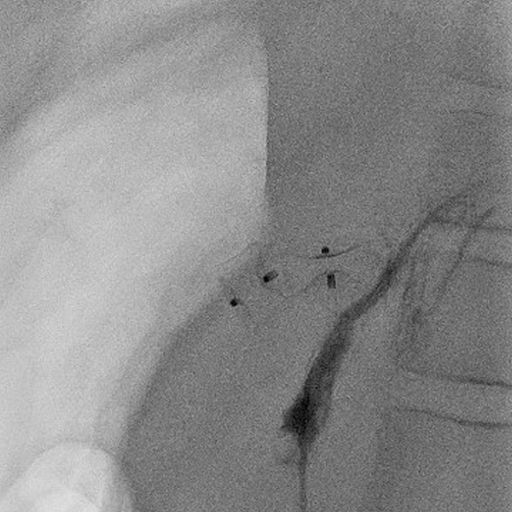

12 jähriger Junge bei dem im Rahmen der Traumadiagnostik nach einem Fahrradunfall eine fokale noduläre Hyperplasie der der Leber auffiel (A). Die weitere Diagnostik ergab den Befund einer Abernethy-Malformation Typ II mit Einmündung der Shuntvene in die linke Nierenvene (B) 3D-Rekonstruktion aus dem CT-Datensatz (PSS-portosystemscher Shunt, VCI-Vena cava inferior, VMS-Vena mesenterica superior, VRS-Vena renalis sinistra). Bei der Katheteruntersuchung (C) mit Ballonblockade der Shuntvenene (Pfeil) zeigt sich ein schmächtiges intrahepatisches Pfortadersystem. Die Druckmessung (E) unter Ballonblockade zeigte keinen signifikanten Druckanstieg. Daher konnte der interventionelle Verschluss der Shuntvene mit 2 Vascular Plugs (D) problemlos durchgeführt werden. Die Herzkatheteruntersuchung (E) zeigte allerdings bereits eine manifeste pulmonale Hypertonie mit einem pulmonalen Mitteldruck von 43 mmHg und einem Widerstands-index von 10 WE x m².